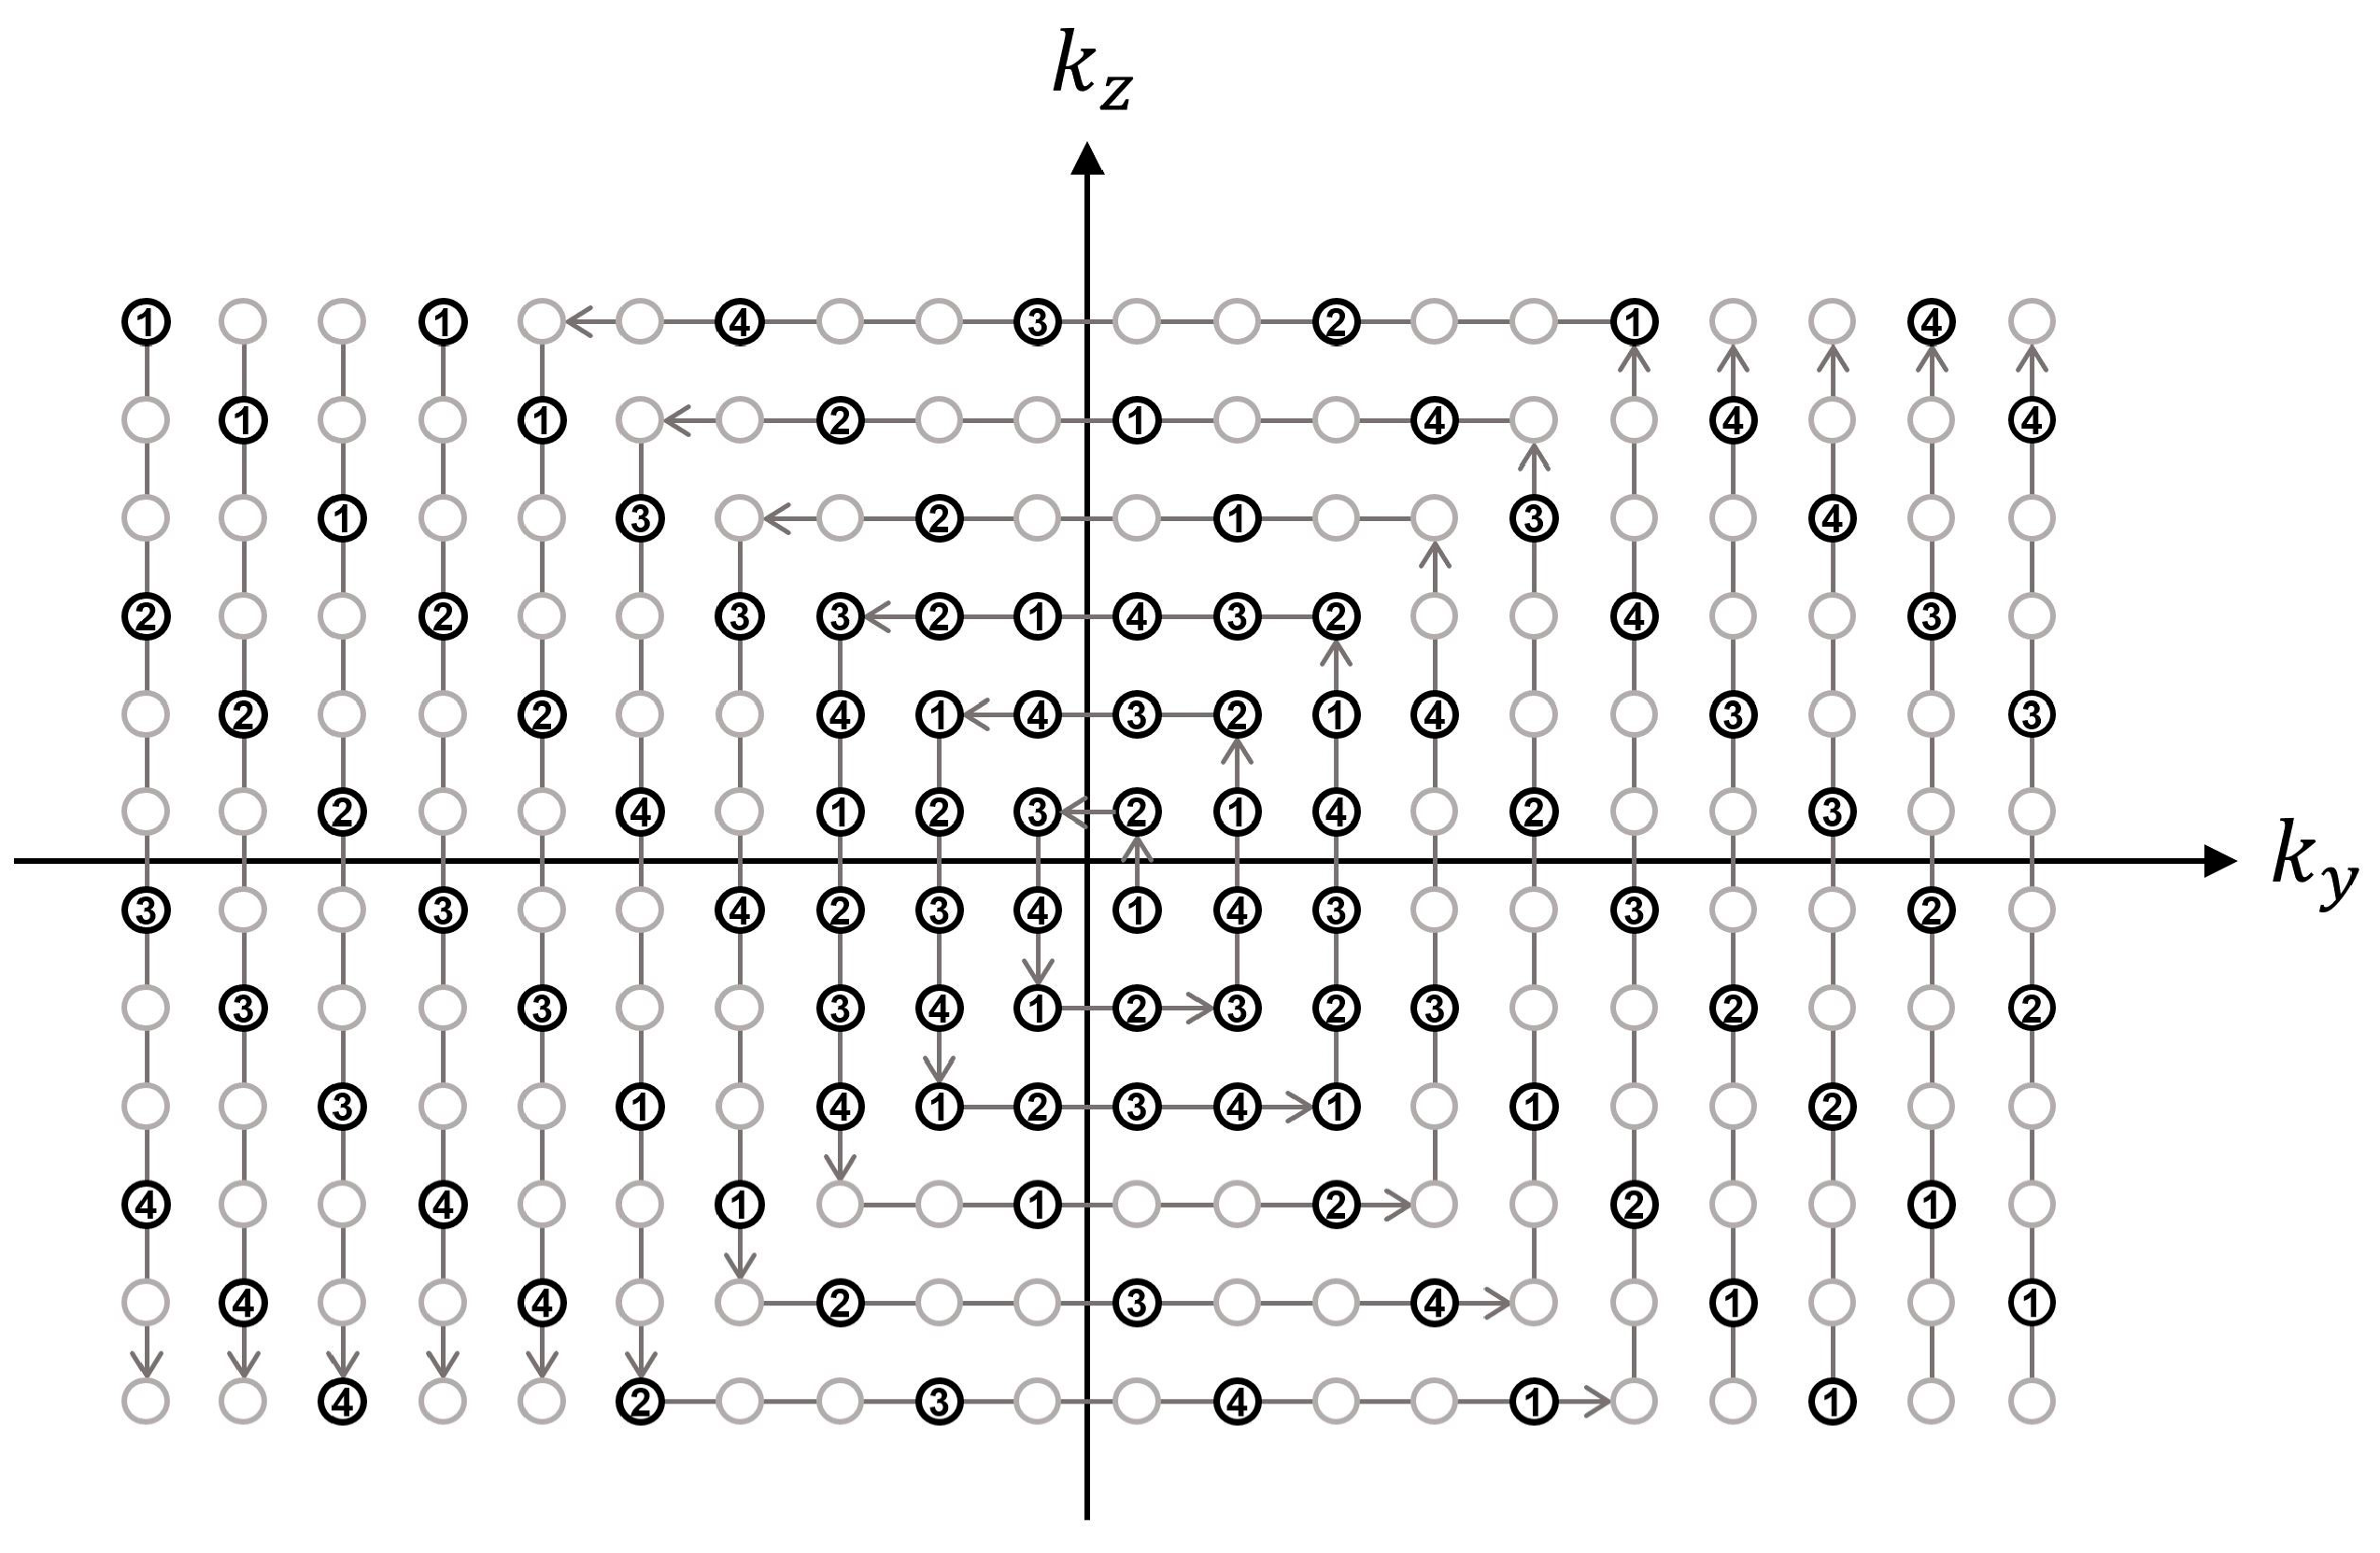

2.2. VS-MRA Pulse Sequence